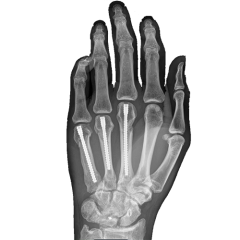

Explore our broad range ofOrthopedic Products

We are dedicated to improving the quality of life of patients suffering with bone and joint problems by delivering the latest medical devices that are proven to be effective and backed by scientific studies and research

• Surgical Devices